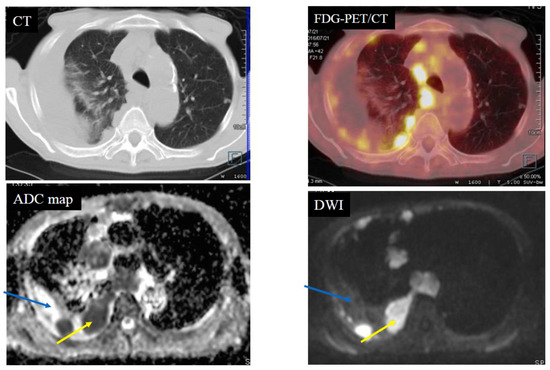

| Diagnosis | MPM | 11 | 0 | 0 | 0 | 11 |

| Pleural dissemination | 1 | 9 | 0 | 0 | 10 | |